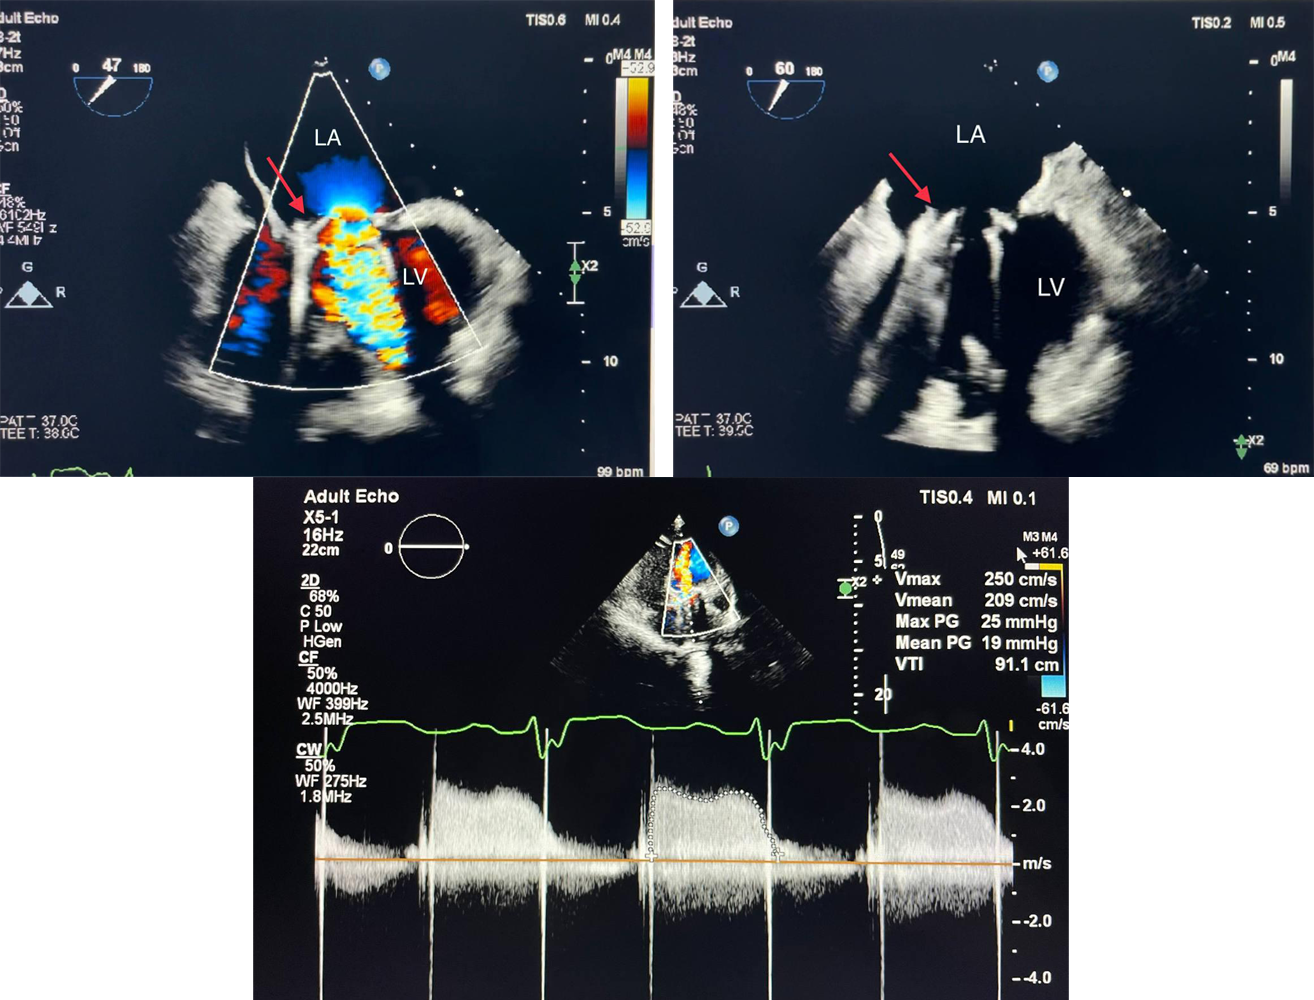

Image of the Week - 21 February 2024

Doctor Raid Faraj

Doctor Nouhaila Lahmouch

Doctor Jamila Zarzur